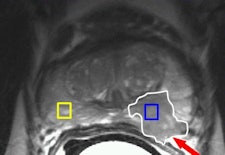

A 56-year-old male with prostate-specific antigen (PSA) level of 11; transrectal ultrasound (TRUS) biopsy, Gleason 3+4 left; DRE T1c. Prostatectomy confirmed Gleason 4+3 prostate cancer (PC) with extracapsular extension (ECE) in left peripheral zone (PZ). Left: Axial T2-weighted MR image shows low-signal lesion in the left PZ (white outline), which fits PC with ECE (arrow, PI-RADS 5). Right: Axial dynamic contrast-enhanced MR image shows asymmetric focal enhancement both in tumor in left PZ, with curve type 3 (PI-RADS 5). All images courtesy of Dr. Jelle Barentsz.

A 56-year-old male with prostate-specific antigen (PSA) level of 11; transrectal ultrasound (TRUS) biopsy, Gleason 3+4 left; DRE T1c. Prostatectomy confirmed Gleason 4+3 prostate cancer (PC) with extracapsular extension (ECE) in left peripheral zone (PZ). Left: Axial T2-weighted MR image shows low-signal lesion in the left PZ (white outline), which fits PC with ECE (arrow, PI-RADS 5). Right: Axial dynamic contrast-enhanced MR image shows asymmetric focal enhancement both in tumor in left PZ, with curve type 3 (PI-RADS 5). All images courtesy of Dr. Jelle Barentsz.Evidence is growing that MRI before the second, or even initial, biopsy can accurately distinguish between those patients who require immediate biopsies and those for whom biopsy can be deferred. A correlation between apparent diffusion coefficient (ADC), calculated from DWI, and Gleason score has been found. MRI before biopsy can help to detect high-grade tumors, which helps target biopsies within areas of low ADC values.